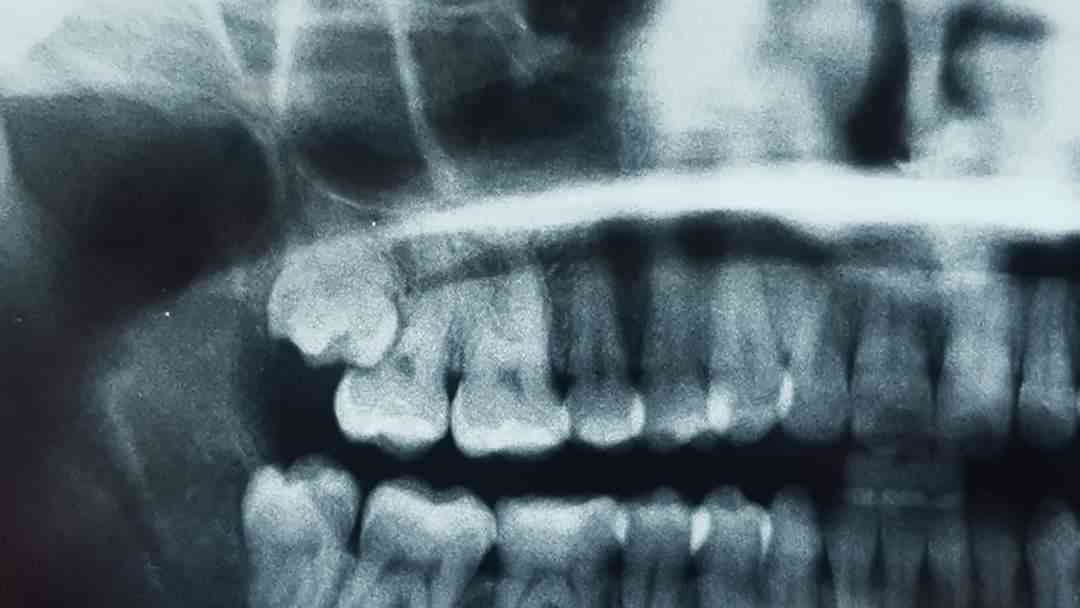

جراحة الفك والأسنان

الأضرار التي تسببها اضراس العقل احيانا. سأعرض اليوم حالة من الحالات في العيادة. منذ ثلاثة ايام اتت مريضة الى العيادة تعاني من الم شديد. بعد الاطلاع على الصورة الشعاعية تبين بأن ضرس العقل قد سبب ت ... اقرأ المزيد